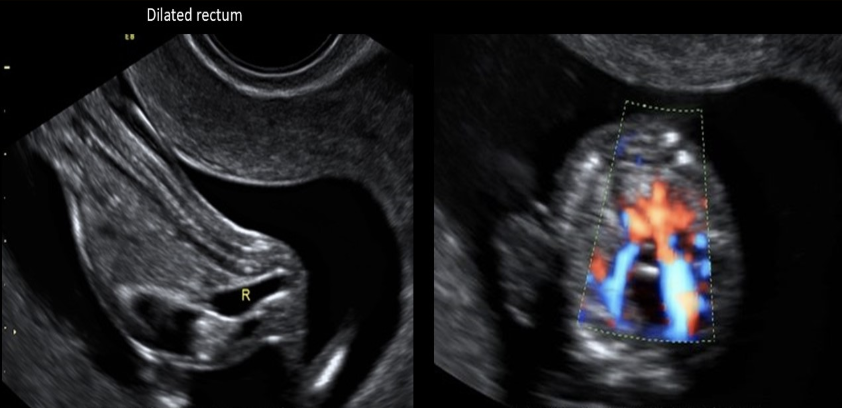

a dilated fetal rectum should raise strong suspicion of

a) posterior urethral valves

b) cystic fibrosis

c) anal atresia

d) jejunal atresia